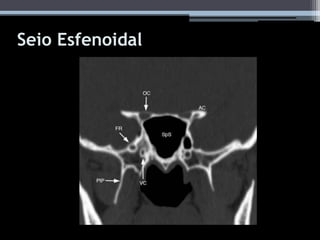

Seio Esfenoidal

• #37 A, Axial CT image shows septated air cells (O) extending into left sphenoidal sinus and anterior clinoid process (asterisk). AnE = anterior ethmoidal air cells, PoE = posterior ethmoidal air cells. B, Coronal CT image shows horizontal septation (arrow) separating smaller left sphenoidal sinus (Sph) below from air cells (O) above. This finding is characteristic of Onodi cells. Axial and coronal images show extensive pneumatization of right sphenoidal sinus with pneumatization of anterior clinoid process (asterisk).